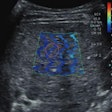

CEUS improves O-RADS diagnostic performance